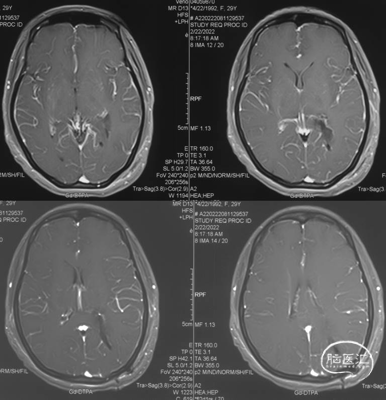

头颅MRI

头颅MRI增强

左侧侧脑室三角区脑膜瘤。

左侧侧脑室三角区占位,边界清楚,不均匀强化,术前诊断良性脑膜瘤相对比较明确;患者年轻女性,无明确阳性体征,对手术微创及功能保留要求比较高;肿瘤相对较小,完全位于侧脑室内,且有明确的脉络丛供血;肿瘤位于三角区且为左侧优势半球,三角区皮层造瘘较大时可能术后会出现语言障碍及视野缺损明显。